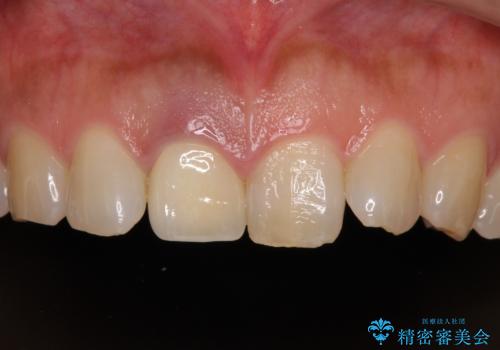

- セラミッククラウンが白すぎる前歯と、放置している奥歯を気にして来院された患者様です。

前歯のセラミッククラウンは将来ホワイトニングをするつもりで白くしたものの、それほど白くならず、ホワイトニングも面倒くさいとのことで白すぎる印象となっていました。

前歯のセラミッククラウンは周りの歯と調和させるためにオーダーメイドタイプのものをおすすめしましたが、元が白すぎていたため、概ね色合いが合えば大丈夫であるとのことで、既製パターンの色調で仕上げました。